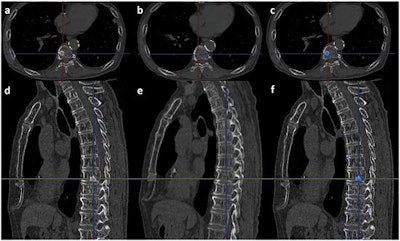

- Finally, the color-coded difference of the 3D model is superimposed on the follow-up monochromatic MPR images. Osteolytic lesions (blue) and osteoblastic lesions (red) are color-coded. The case below shows vertebral metastases diagnosed by the CAD software.

The detection of vertebral metastases with and without CAD. Image republished courtesy of PLOS One, January 17, 2016.